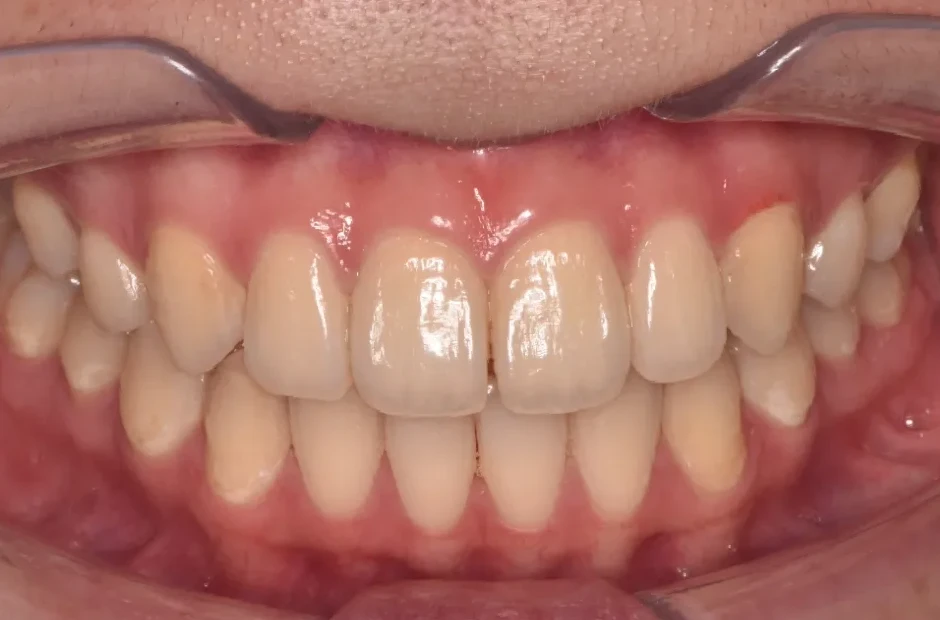

上顎前突、叢生

| 診断名・主訴 | 上顎前突、叢生 |

|---|---|

| 年齢・性別 | 26歳・女性 |

| 治療期間・回数 | 2年 |

| 治療に用いた主な装置 | 舌側ブラケット |

| 抜歯部位 | 上顎4,4 |

| 治療費 | 100万円(税抜) |

| リスク・副作用 | 装置による違和感・疼痛・歯肉退縮・歯根吸収・虫歯のリスクなど |

治療前

治療中

治療後